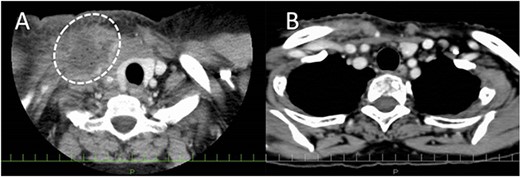

A 77-year-old man underwent a total laryngectomy with modified bilateral ND for advanced laryngeal squamous cell carcinoma (cT4aN0M0, stage IVA). A small chylous leakage was observed on postoperative day (POD) 1. As the chylous leakage did not improve with fasting, wound compression, and drainage, ligation of the thoracic duct and its branches was attempted under general anesthesia on POD3. However, the leakage persisted, and computed tomography (CT) on POD17 revealed a lymphatic cyst extending from the peritonsillar space to the upper mediastinum (Fig. 1A). Therefore, we decided to administer OK432 sclerotherapy. After draining the leaked chyle, we injected 2KE of OK432 diluted with 4 mL of normal saline and compressed the wound. The day after the injection, the chylous leakage completely stopped without complications. Seven days after the first injection, a second dose of OK432 was administered in a similar manner. CT on POD 83 confirmed the complete disappearance of the retained lymph (Fig. 1B).

Enhanced CT before and after OK432 injection. (A) Before OK432 injection. Cervical CT shows a chylous leakage in the left supraclavicular fossa. (B) After two cycles of OK4432 injection. The chylous leakage completely disappeared after OK432 sclerotherapy.